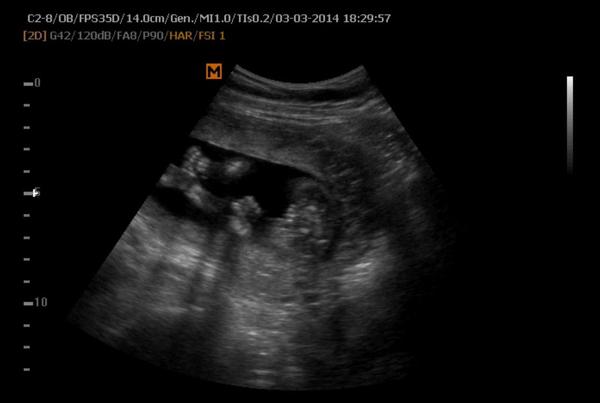

Takže prosím, jsem 12+1 - vše je v pořádku jen nám nechce říct pohlaví - dostali jsme fotky a jedna z nich - viz příloha, mi přijde že je to kluk . Holky,odbornice - měly jste něco podobného a co se z toho vyklubalo?